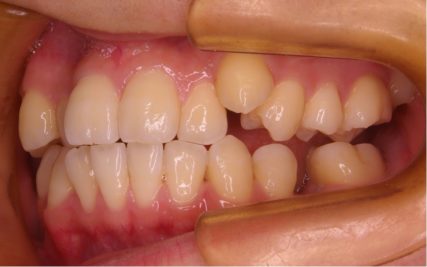

- 治療前

- 上下とも前歯のスペース不足が認められた。歯のサイズと顎の幅とのバランスが不調和な事が原因の1つとして考えられる。

- 治療後

- 前歯部のでこぼこが解消され、正常咬合を獲得する事が出来た。又、歯科矯正用アンカースクリューを用いる事で抜歯スペースを有効に利用できた。